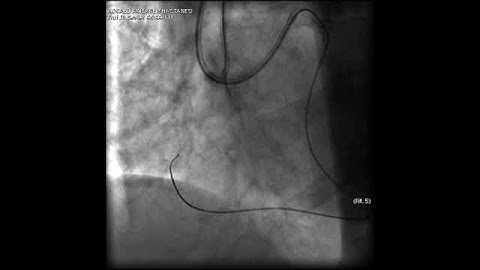

Aortic dissection and radial rupture during retrograde CTO PCI: Management of complications VİDEO 15